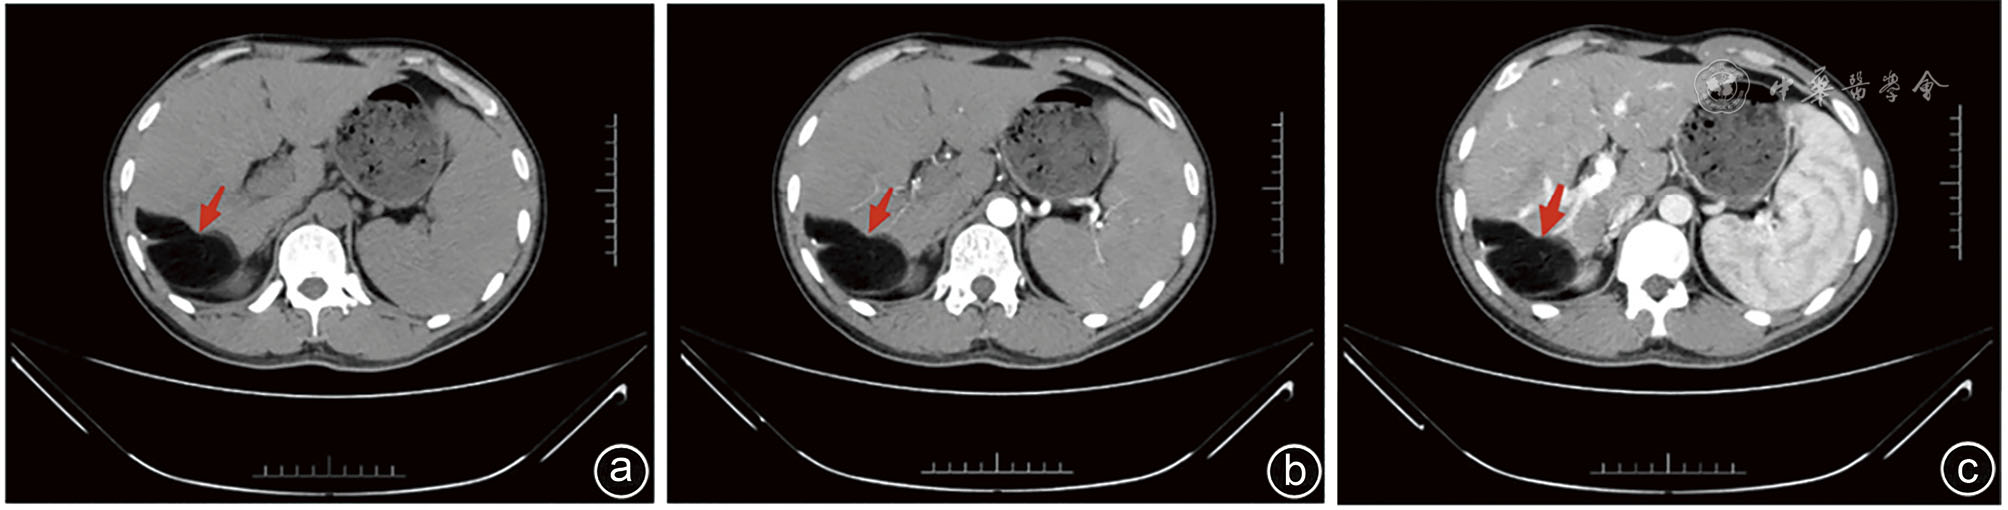

图2 一例肝右后叶包膜下脂肪瘤患者术前腹部MRI图像 注:a为T1像;b为T2像;c为增强扫描;肝右后叶肝包膜下可见不规则状 T1、长T2信号影,边界清楚,增强后无强化(红色箭头所示)

Clinical data of a 32-year-old male patient with hepatic lipoma admitted to Department of Hepatobiliary and Pancreatic Surgery of the Second Affiliated Hospital of Kunming Medical University in November 2023 were retrospectively analyzed. He was hospitalized due to a liver-occupying mass during physical examination. Physical examination revealed nontender abdomen. Complete blood count, blood biochemistry, coagulation function and AFP level was detected normal, while CA50 level was increased. Abdominal ultrasound showed hyperechoic area in the space between liver and kidney. Contrast-enhanced ultrasound revealed that the lesions showed uneven and slight hypoenhancement in the early stage and hypoenhancement in the late stage. Abdominal contrast-enhanced CT showed subcapsular fat density shadow in the right posterior lobe of liver. MRI showed round-like long T1 and long T2 signal shadows in the subcapsular area of the right posterior lobe, without enhancement. Spleen was significantly enlarged. No abnormality was found in parenchymal signals, and no enhancement was observed. MRCP showed no dilatation was seen in the intra-and extra-hepatic bile ducts. Literature review about liver lipoma was conducted and the experience of diagnosis and treatments was summarized.